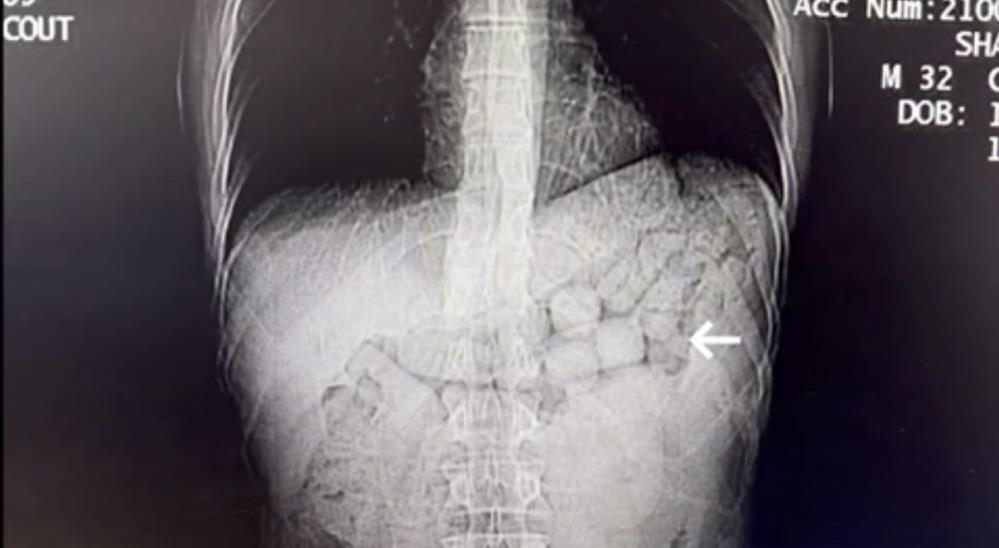

Tomografide yabancı cisim görüldü

Polis ekipleri, şüphelilerin uyuşturucuyu midelerinde taşıdığından şüphelenerek şahısları hastaneye sevk etti. Hastanede çekilen tomografi görüntülerinde, şüphelilerin mide ve bağırsak bölümlerinde çok sayıda yabancı cisim olduğu tespit edildi.

Hastanede doktor gözetiminde yaklaşık 3 gün süren doğal çıkarma işlemi sonucunda, şahısların vücudundan 91 kapsül halinde toplam 807,15 gram metamfetamin maddesi ele geçirildi. Tedavilerinin ardından gözaltına alınan ve emniyetteki işlemleri tamamlanan şüpheliler, sevk edildikleri adli makamlarca tutuklanarak cezaevine gönderildi.